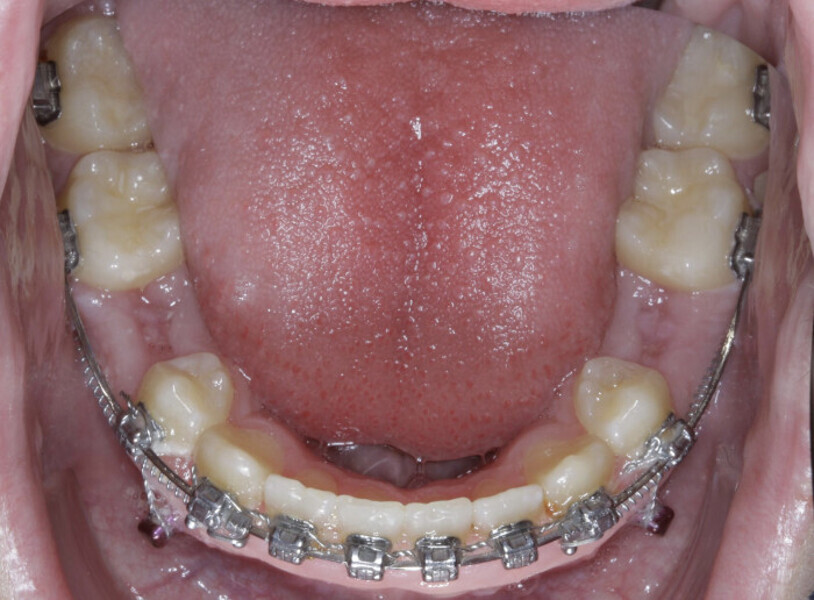

New Age orthodontics and orthopaedics with temporary anchorage devices